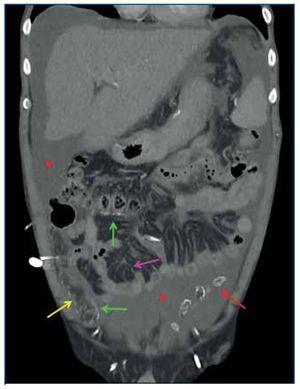

Figura 3.Tomografía computarizada abdominopélvica tras administración de contraste intravenoso, reconstrucción coronal. Se observa engrosamiento y realce aumentado del peritoneo parietal (flecha amarilla) y del peritoneo visceral (flecha verde), calcificaciones «en sábana» del peritoneo visceral, engrosamiento del mesenterio de las asas intestinales (flecha rosa) por el desarrollo de membranas fibróticas que retraen las asas de intestino delgado adyacentes, asas de intestino delgado de diámetro intraluminal disminuido (asterisco amarillo) y ascitis loculada perihepática, periesplénica, en ambas gotieras paracólicas y en pelvis (asterisco rojo).

Figura 4.Tomografía computarizada abdominopélvica tras administración de contraste intravenoso, reconstrucción coronal, corte más anterior que el de la figura 3. Se observan calcificaciones «en sábana» del peritoneo parietal (flecha amarilla) y del peritoneo visceral (flechas verdes), conglomerados de calcificaciones del peritoneo visceral (flecha roja), engrosamiento del mesenterio de las asas intestinales (flecha rosa) por el desarrollo de membranas fibróticas que retraen las asas de intestino delgado adyacentes, y ascitis loculada (asteriscos rojos).

Los signos radiológicos de la PE se pueden dividir en tres categorías: anomalías del peritoneo, anomalías en las asas de intestino delgado y la presencia de colecciones líquidas o ascitis loculada3.

La afectación del peritoneo se caracteriza por un engrosamiento de este primero en forma de placas aisladas y más tarde difuso, afectando tanto a la capa de peritoneo visceral como a la parietal3 (figuras 1 y 3). En los estudios de TC realizados tras la administración de contraste intravenoso se puede observar el realce aumentado del peritoneo engrosado2 (figura 3). Las calcificaciones que se producen en el peritoneo comienzan siendo lineales, como pequeñas placas, y evolucionan a calcificaciones «en sábana» (figuras 1-4) y en forma de conglomerados2,3 (figura 4).

Las asas de intestino delgado aparecen engrosadas, con una disminución de su diámetro intraluminal (figuras 1, 3 y 4) y de localización central. También se pueden observar calcificaciones de sus paredes. Como resultado de las membranas fibróticas que se desarrollan envolviéndolas (figuras 2, 3 y 4), la raíz del mesenterio se retrae y se origina un conjunto de adherencias internas, que pueden causar una obstrucción de intestino delgado. En este último caso, las asas se mostrarán dilatadas y como complicación se puede producir necrosis y perforación de estas2,3.

Los pacientes con DP inevitablemente tendrán ascitis3 y, debido al engrosamiento y la fibrosis de las membranas peritoneales, será una ascitis loculada (figuras 1, 2, 3 y 4), que contribuye a la distribución central de las asas de intestino delgado3.